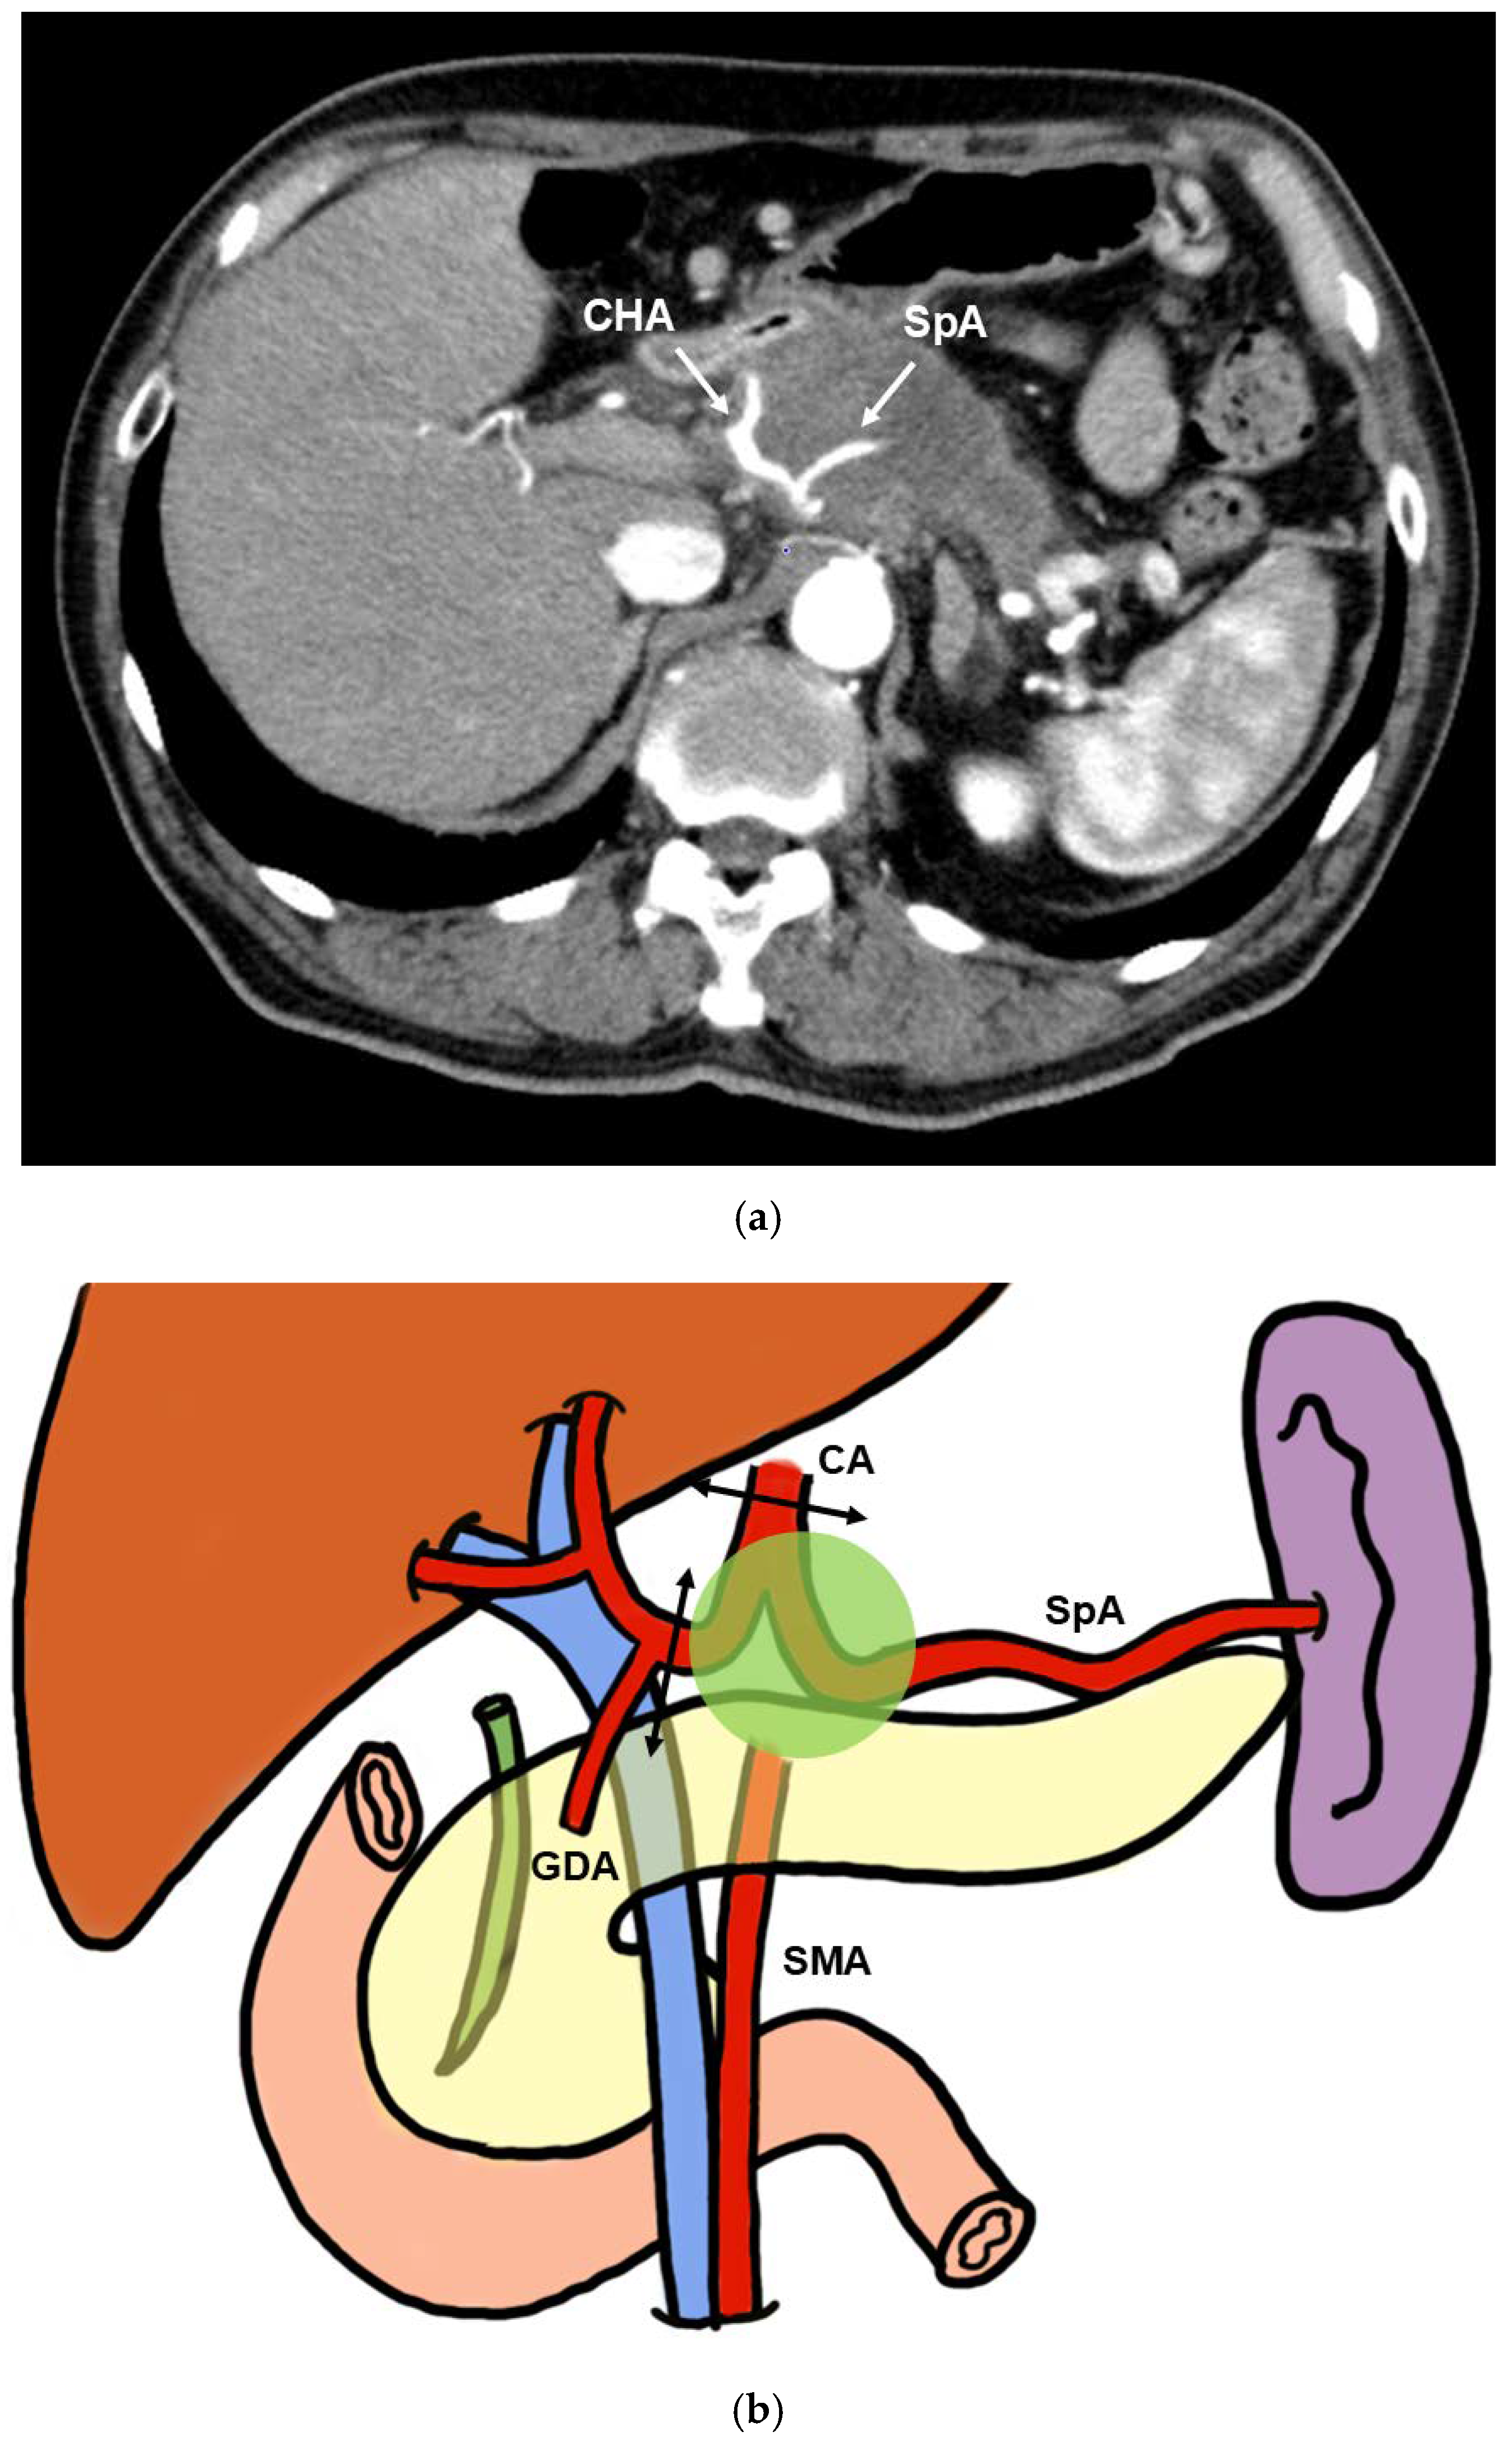

2.2.3. PD-CAR and TP-CAR(Spleen Preserving)

2.3. CA Resection and Reconstruction

CA Reconstruction in TP-CAR+TG

CA Reconstruction in PD-CAR and TP-CAR(Spleen Preserving)